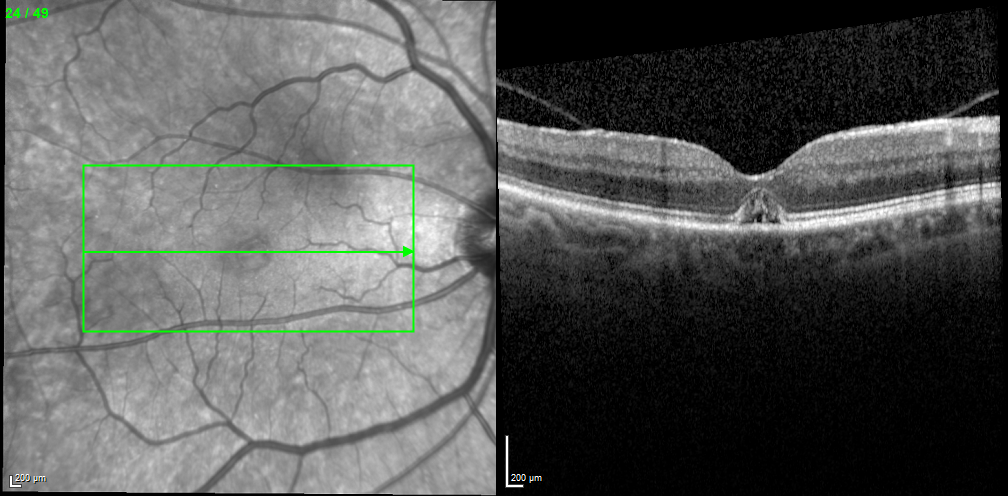

His fundus exam revealed macular edema OD; it was normal OS. Spectralis OCT (Heidelberg Engineering) high-speed 25-raster macular scans through, above, and below the fovea OD revealed macular edema and subretinal fluid (Figure 1). As the appearance was suggestive of a macular hole (MH), a high-density OCT scan was performed, revealing a small MH missed during the standard OCT scan (Figure 2).

<p>Figure 1. Standard OCT scan through the fovea (A), above it (B), and below it (C).</p>

Figure 1. Standard OCT scan through the fovea (A), above it (B), and below it (C).